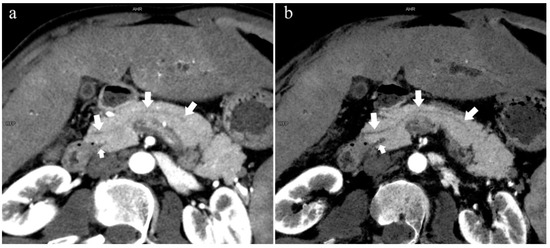

There were 109 patients in the variant group. The PD (type 4) was the most common pancreatic variant (6.2%, 50/808), including type 4b (3.5%, 28/808, Figure 6), complete PD (type 4a) (1.6%, 13/808, Figure 7), and incomplete PD (type 4c) (1.1%, 9/808, Figure 8). The frequency of type 3a was 0.6% (5/808, Figure 9), and that of reverse PD (type 3c) was 3.6% (29/808). The frequency of type 2 was 2.4% (19/808), including type 2a (1.5%, 12/808) and type 2b (0.9%, 7/808, Figure 10). Anza pancreatica (type 5) was relatively rare (0.7%, 6/808), including type 5a (0.6%, 5/808) and type 5b (0.1%, 1/808).

Figure 9.

Type 3a. A 49-year-old male patient with IPMN. (a): MIP [45 keV MEI (+)] shows the enlarged head of the pancreas with tumor (pentagram), and tortuous dilation of MPD (long arrow) and APD (short arrow). The APD communicates with the front segment of the MPD without flowing into the MiP. The drainage tube (arrow) can be seen in the MPD. (b): MinIP [45 keV MEI (+)] reduces the interference of ductal artifacts and shows the course and more detail of the distal pancreatic duct. Postoperative pathology confirmed that the mass was IPMN.

Figure 10.

Type 2b. A 45-year-old female patient with Cholangitis. (a): MIP [45 keV MEI (+)] shows MPD (long arrow) flows into MiP and extends to the tail of the pancreas. The tiny APD (short arrow) communicates with the front segment of the MPD without flowing into the MP. (b): MinIP [45 keV MEI (+)] shows the overall configuration of the pancreatic duct and the thin duct in the tail. MPD refers to anatomically large and functionally dominant ducts.